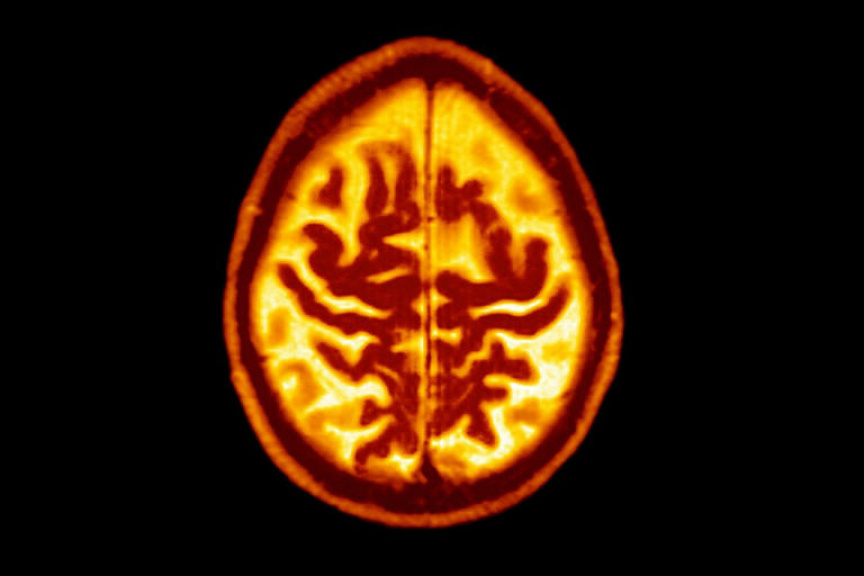

ވޮޝިންޓަން ޔުނިވާސިޓީ ސްކޫލު އޮފް މެޑިސިންގެ ރޭޑިއޮލޮޖީ ޑިޕާޓްމަންޓްގައި އެސިސްޓެންޓް ޕްރޮފެސަރެއްގެ ގޮތުގައި މަސައްކަތްކުރާ ޑރ. ސައިރަސް ރާޖީ ވިދާޅުވި ގޮތުގައި އަމިލޮއިޑު އަދި ޓައުގެ އަލާމާތްތައް ފެންނަ ވަރަކަށް ސިކުނޑި ބަލިކަށިވުމުގެ ފުރުސަތު ބޮޑުވެއެވެ. ސިކުނޑީގެ ލޭ ދައުރުވުން ދަށްވުމަކީ ވެސް ސިކުނޑި ބަލިކަށިވުމުގެ އަލާމާތް ދެނެގަނެވޭނެ ކަމެއް ކަމަށް ސައިރަސް ރާޖީ ވަނީ ވިދާޅުވެފައިވެއެވެ.

ރާޖީއާއި އޭނާގެ ޓީމުން މިދިޔަ އަހަރުގެ ނޮވެމްބަރު މަހު ނެރުނު ޕައިލެޓް ދިރާސާއަކުން ދައްކާ ގޮތުގައި ވިސެރަލް ފެޓް ނަމަކަށް ކިޔާ ބަނޑުގެ ފެޓްގެ ބާވަތެއް، އުމުރުން 40 އަހަރާއި 50 އަހަރުން މަތީގެ 32 ފިރިހެނުންނާއި އަންހެނުންގެ ސިކުނޑީގައި އިންފްލެމޭޝަންއާއި އެމިލޮއިޑް އުފެދުމާ ގުޅިފައިވެއެވެ.